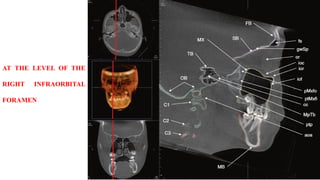

AT THE LEVEL OF THE

RIGHT INFRAORBITAL

FORAMEN

AT THE LEVELOF THE RIGHT INFRAORBITAL FORAMEN